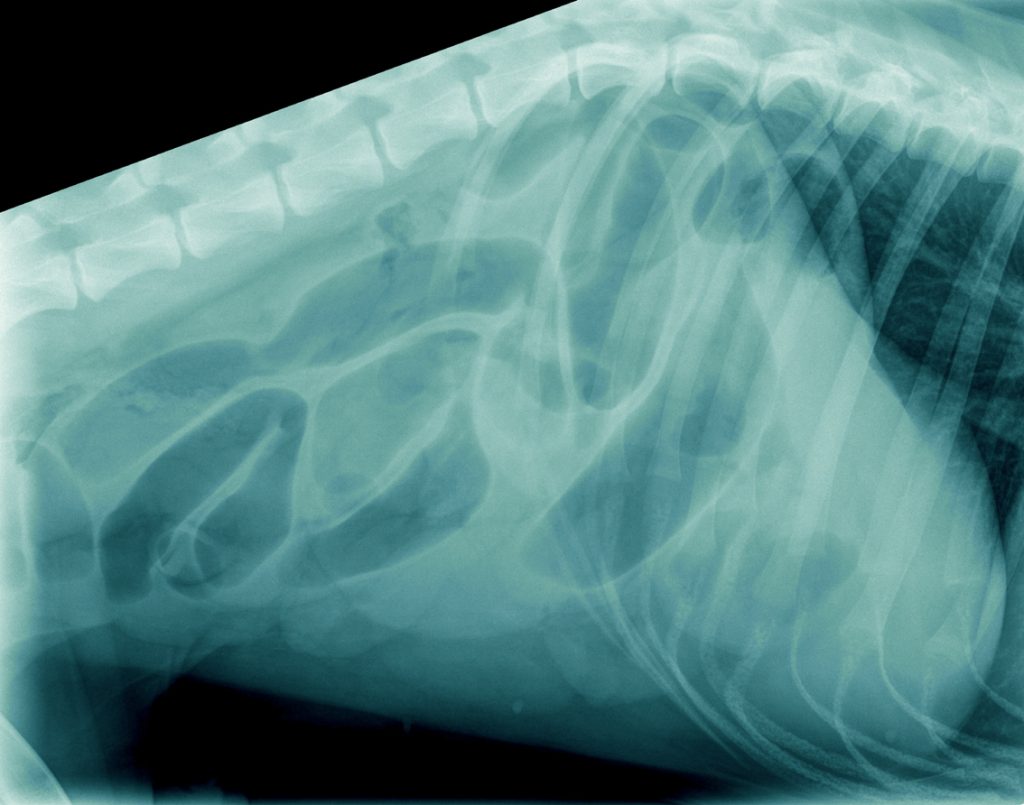

Op het spreekuur kwam T-Bone, een Duitse Herder reu van 1 jaar oud uit Tiel, die sinds een week wat slechter at, af en toe wat braakte en diarree vertoonde. Ondanks medicatie tegen overgeven bleef hij braken en na een paar dagen had hij geen ontlasting meer, alleen wat brij. Dit was reden om opnieuw naar de dierenarts te gaan. De röntgenfoto’s, die gemaakt werden, lieten veel lucht in het maagdarmkanaal zien. Dit kan onder andere wijzen op een verstopping.

Omdat de hond verder niet ziek was en de buik niet gevoelig, werd besloten om de röntgenfoto’s na een dag te herhalen. Hierop was er geheel geen verbetering zichtbaar in de buik ten opzichte van de dag ervoor.